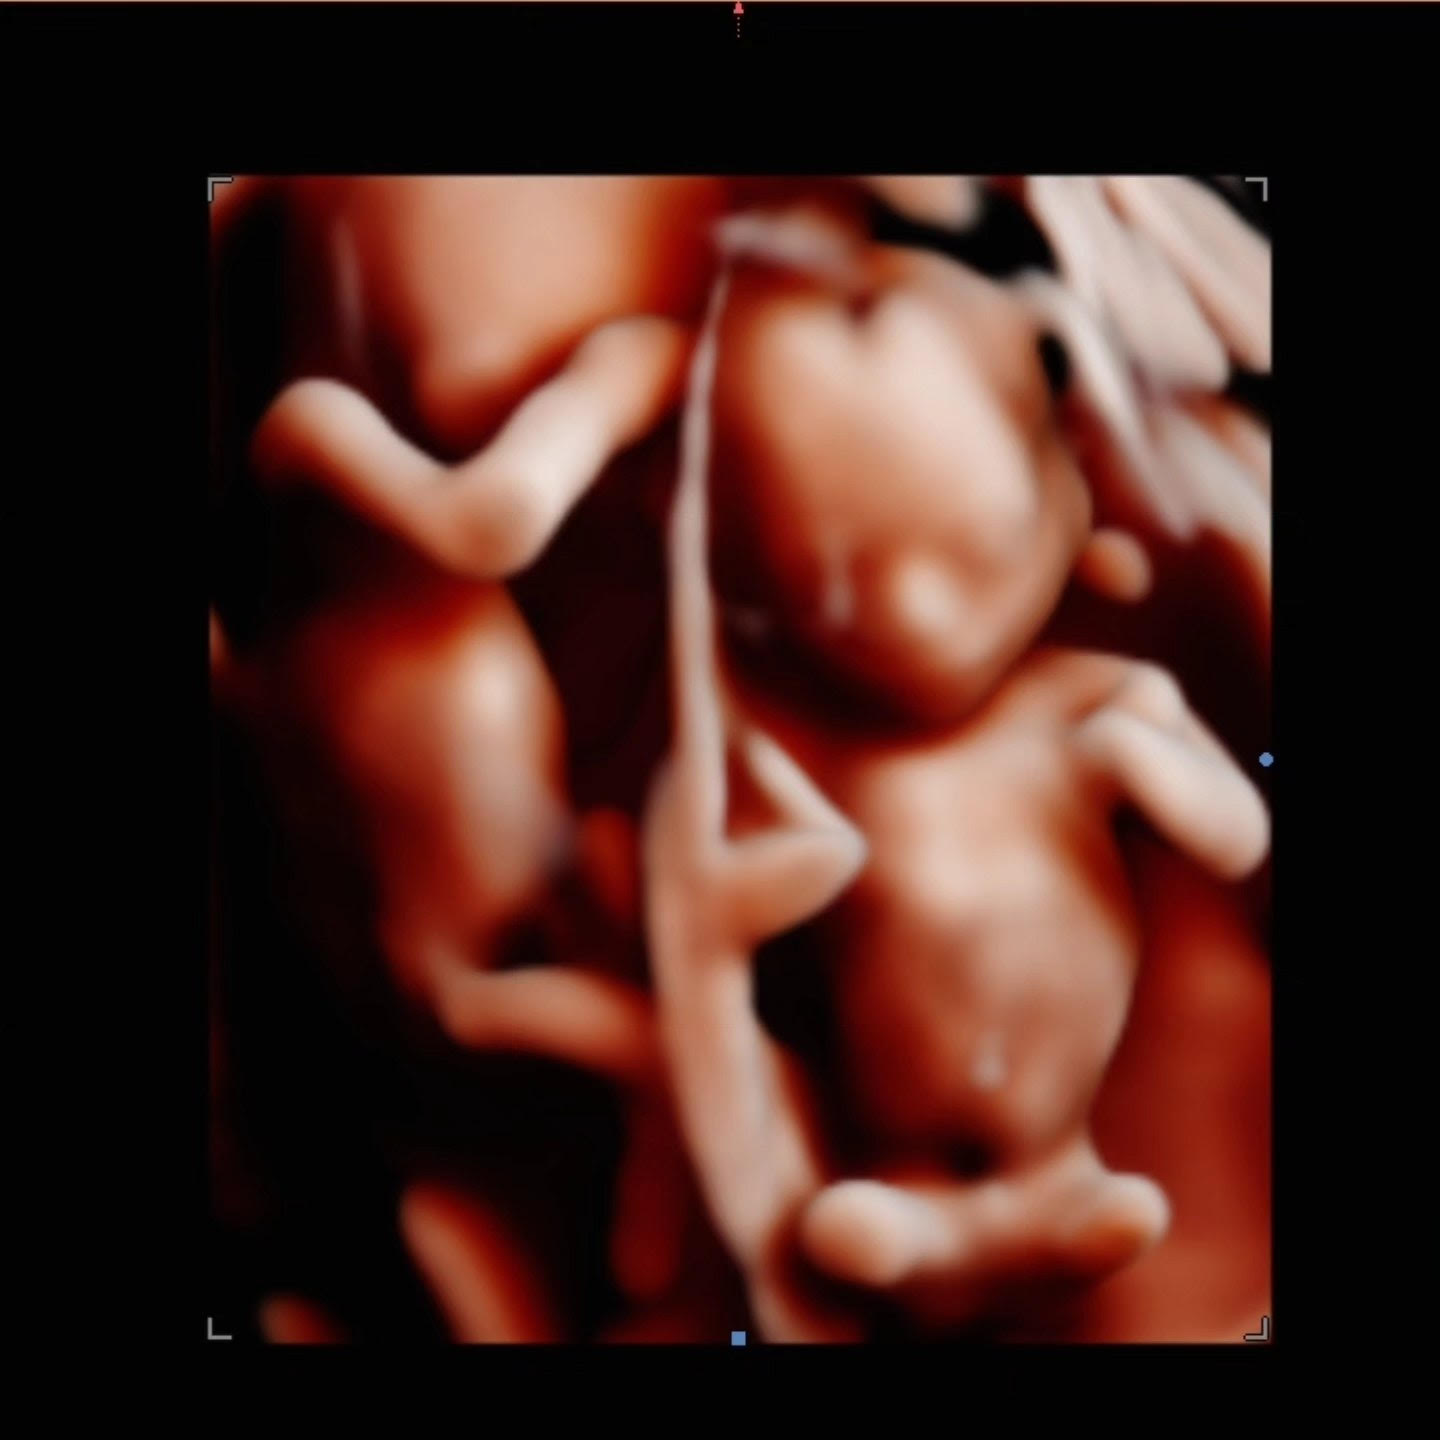

Browsing our 4D ultrasound photos gives you a clear idea of what your session can look like. You will see a range of images, from early 2D visits and gender reveal moments to rich 3D, 4D, and HD live facial detail captured during the most popular weeks between 26 and 32 weeks. Babies are unpredictable, but we have spent many sessions helping families get those sweet expressions, tiny stretched arms, and peaceful faces that you will want to hold onto for years.

Your session at Behind the Bump HD begins with your comfort. We start with 2D imaging to locate baby and find the best viewing angle, then move into 3D, 4D, and HD live ultrasound when position allows. Most visits last between 10 and 25 minutes of scanning time depending on your chosen package, and we take the time to try different positions and techniques to capture the clearest possible views.

Image clarity depends on factors like baby’s position, amniotic fluid levels, and gestational age. If your heart is set on detailed facial images, booking between 26 and 32 weeks gives you the best chance of seeing those fuller features and that characteristic stillness babies often have later in pregnancy.